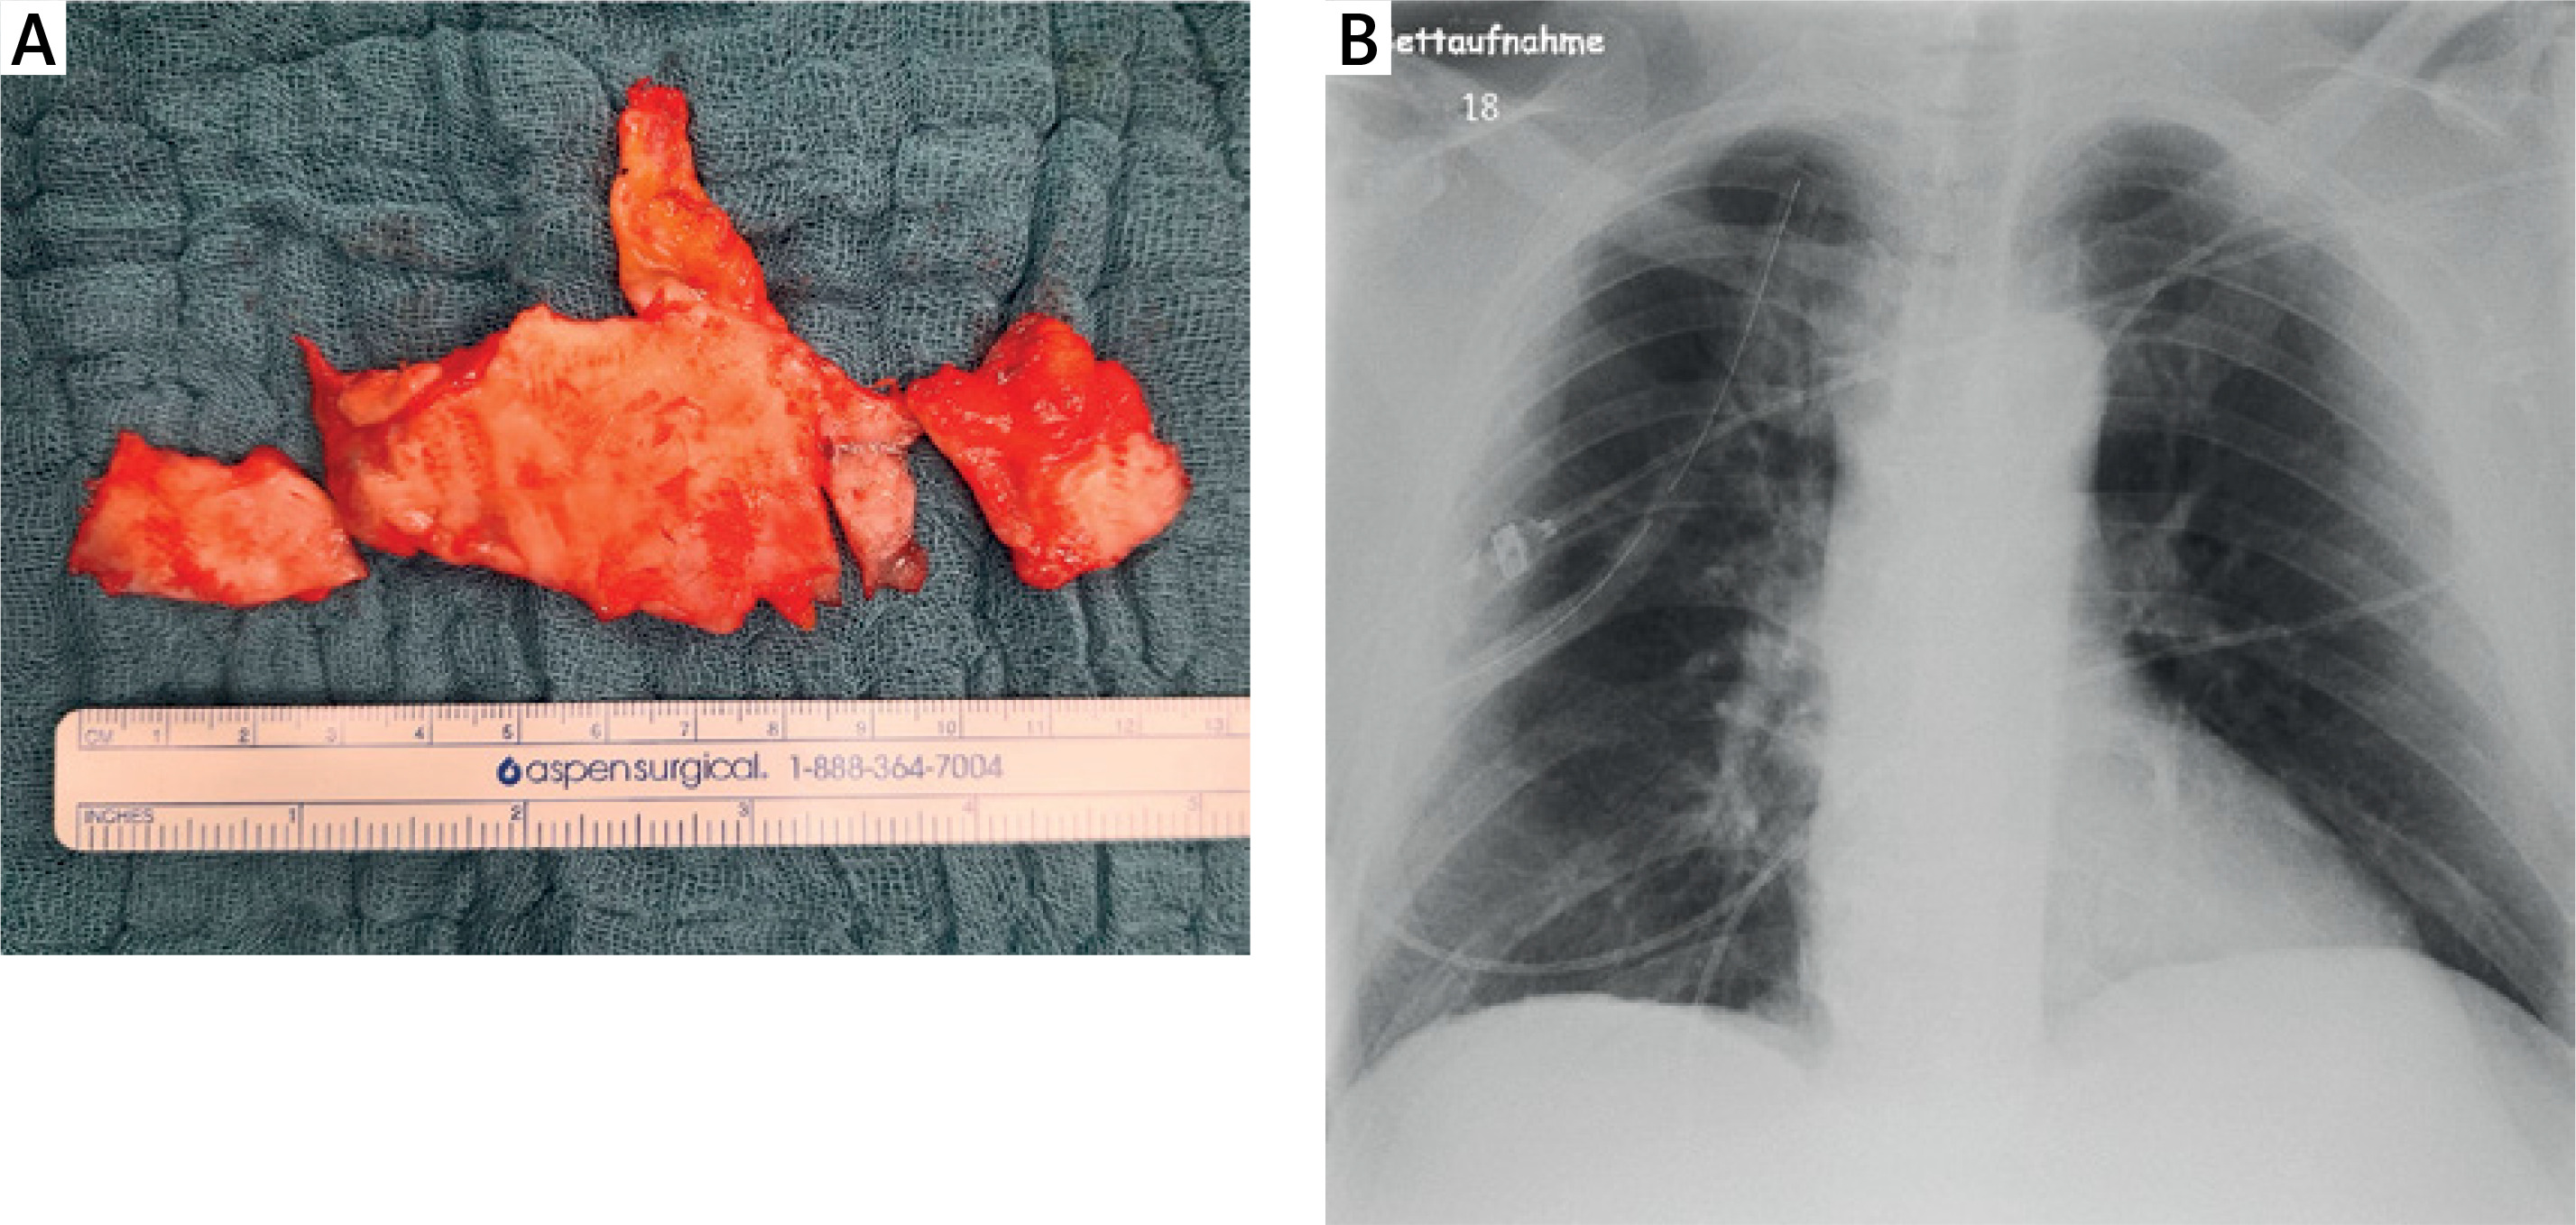

Figure 1

Computed tomography (CT) scan images showing calcified plaques in the parietal pleura (arrows). A – Transverse plane scan of the thoracic cavity. B – Coronal reconstruction highlighting the distribution of pleural plaques